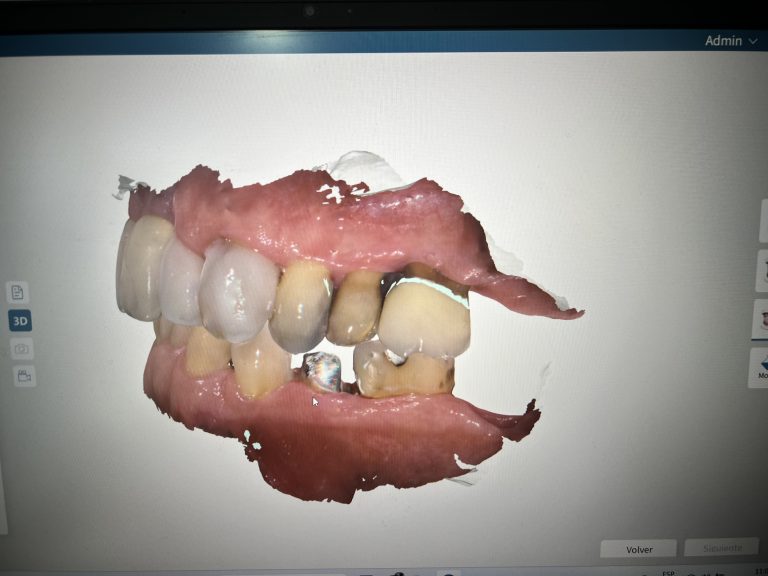

- Scanner Intraoral Digital para Impresiones de Incrustaciones y Coronas